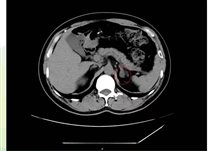

对于肾上腺腺瘤的诊断,需要综合运用多种检查手段。实验室检查如激素水平测定,有助于判断肿瘤是否具有功能性以及分泌的激素类型。影像学检查,如CT、MRI等,能够清晰地显示肿瘤的位置、大小、形态等特征,为诊断和治疗提供重要根据。

如果体检发现肾上腺腺瘤,首先要明确它是否“有功能”:通过CT或MRI明确腺瘤的大小、位置、形态,帮助判断性质。

肾上腺腺瘤CT表现

1.肾上腺腺瘤发生于肾上腺皮质,含脂质;

2.直径多小于3cm;

3.CT值<10HU;

4.出血、坏死、囊变少见;5.CT增强:早期快速廓清